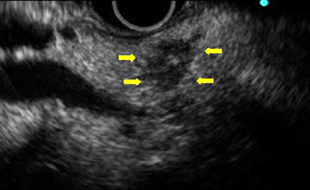

• 超音波内視鏡検査

超音波内視鏡を使用することで、10mm以下の膵がんを発見できることもあります。

• 超音波内視鏡検査(主に胆膵疾患を対象とした検査)